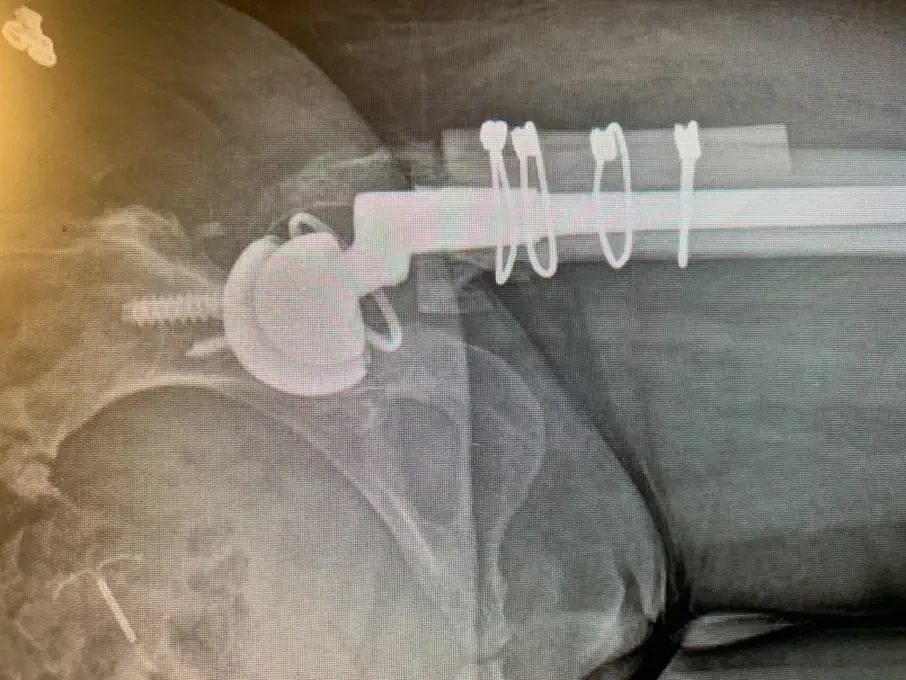

A lateral approach to the hip was used, and despite the patients’ abnormal anatomy, exposure of the hip was gained and the broad, shallow acetabulum was identified. The true acetabulum was identified, and the acetabular component was reamed for and placed without event, augmenting fixation with screws.

Accessing the femoral canal proved challenging, the femoral component was prepared. A femoral shortening osteotomy was then performed removing a significant amount of bone to allow for the hip to be relocated without excessive force. Once this was completed, the definitive femoral component was placed, the osteotomy was fixed and held together with the removed bone acting as autologous bone graft and the hip was relocated.